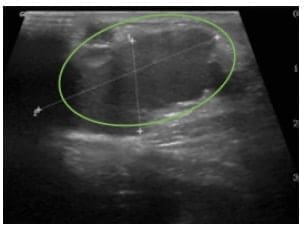

La ecografía abdominal informó una lesión quística multiseptada versus estructuras cilíndricas vasculares dilatadas de 13×3,2×2,1 cm, sin flujo Doppler en su interior, sin componente sólido (Figura 2).

Figura 2. En la ecografía se observa una estructura cilíndrica dilatada y anecoica que se continúan con una de mayor de tamaño, de contornos lobulados, bien definida e hipoecoica, con septos en su interior 3,5 x 1,6 cm. No se identifica componente sólido o calcificaciones y no presenta flujo al aplicar el Doppler color.

Fuente: Imágenes tomadas del registro institucional